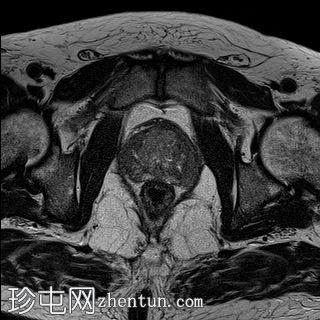

轴位

T2加权像

外周带 (PZ):

T2WI:双侧外周带弥漫性、不均匀低T2信号,范围>15 mm,尖端后内侧可见小片相对保留的病灶。左侧尖端及腺体中部可见包膜隆起。评分5/5。

DWI/ADC:高b值DWI呈弥漫性高信号,ADC呈相应低信号(扩散受限)。评分5/5。

DCE:早期强化阳性。

PI-RADS:5 - 极高风险(极有可能存在临床意义的癌症),考虑炎症性病变。

肉芽肿性前列腺炎是多参数磁共振成像 (mpMRI) 中一种重要的、与临床意义显著的前列腺癌相似的疾病,因为它可以产生明显的周围带异常,伴有扩散受限和早期强化,通常导致较高的 PI-RADS 分级。

在本病例中,mpMRI 显示双侧周围带弥漫性 T2 低信号,高 b 值 DWI/ADC 图像上呈扩散受限,早期强化阳性,并伴有包膜轮廓隆起。这种影像学表现可能类似于浸润性或广泛性周围带癌,尤其是在 PSA 升高和直肠指检异常的情况下。然而,炎症性疾病,特别是肉芽肿性前列腺炎,可能出现类似的影像学表现。经直肠前列腺活检的组织病理学检查显示,患者患有严重的慢性非干酪性肉芽肿性前列腺炎,未见肿瘤证据。